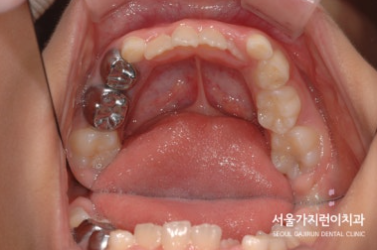

오늘은 상악의 돌출 케이스를 설명해볼텐데요. 치아의 배열 공간이 심하게 부족했던 성장기 환자의 비발치 교정이기 때문에 좀 더 까다로운 교정과정일 수밖에 없었습니다. 환자 분의 경우 상악골의 과성장과 하악골의 열성장이 종합적으로 발현된 케이스로 상악괄의 과성장을 조절하고 상악 견치 및 소구치의 맹출 공간을 확보하기 위해 상악 어금니의 후방이동이 필요했는데요. 그 과정에서 헤드기어라는 장치를 이용한 치아교정이 이루어졌습니다.

이후에는 돌출감을 해소하기 위한 미니스크류를 활용한 치아교정이 이루어졌는데요. (미니스크류는 잇몸에 박혀있는 작은 나사와 같은 장치를 말합니다. ) 미니스크류는 간단한 국소마취로도 식립이 가능하고 잇몸뼈에 직접 식립하기 때문에 강력한 고정힘으로 정밀하게 치아이동이 가능한데요. 치료를 하지 않았다면 치아의 배열이 심하게 비뚤어지고 상악 전치가 뻐드러졌을 것을 1차 성장교정(헤드기어)를 통해 만족할 수 있는 경과를 만들어냈습니다.